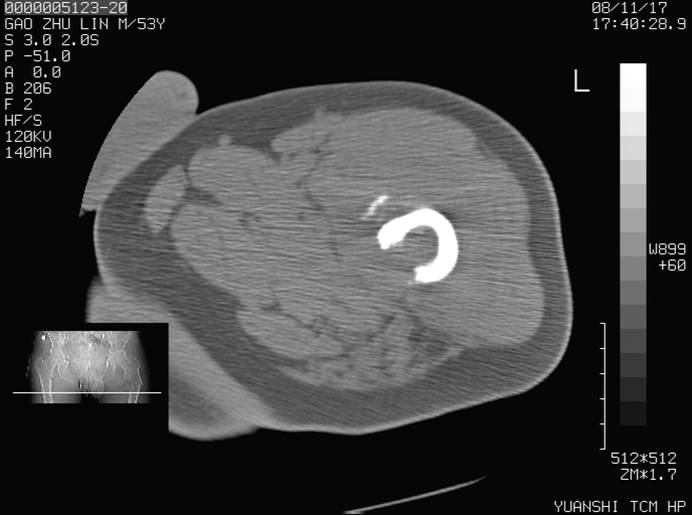

标题: CT16696:M53Y,左股骨上段骨折。 [打印本页]

标题: CT16696:M53Y,左股骨上段骨折。

左股骨上段外伤1个小时,左股骨上段疼痛。村医以腰椎间盘病变给以按摩及理疗数天。

图像不太清楚,左股骨上段外伤性骨折?病理性骨折?

左股骨上段粉碎性骨折

左股骨上段粉碎性骨折;建议上传骨窗看看是不是病理性的啊!

左股骨上段粉碎性骨折,不排除病理性骨折可能。

考虑骨肉瘤伴病理骨折

考虑:骨肉瘤伴病理骨折.

病理性骨折,考虑转移所致.